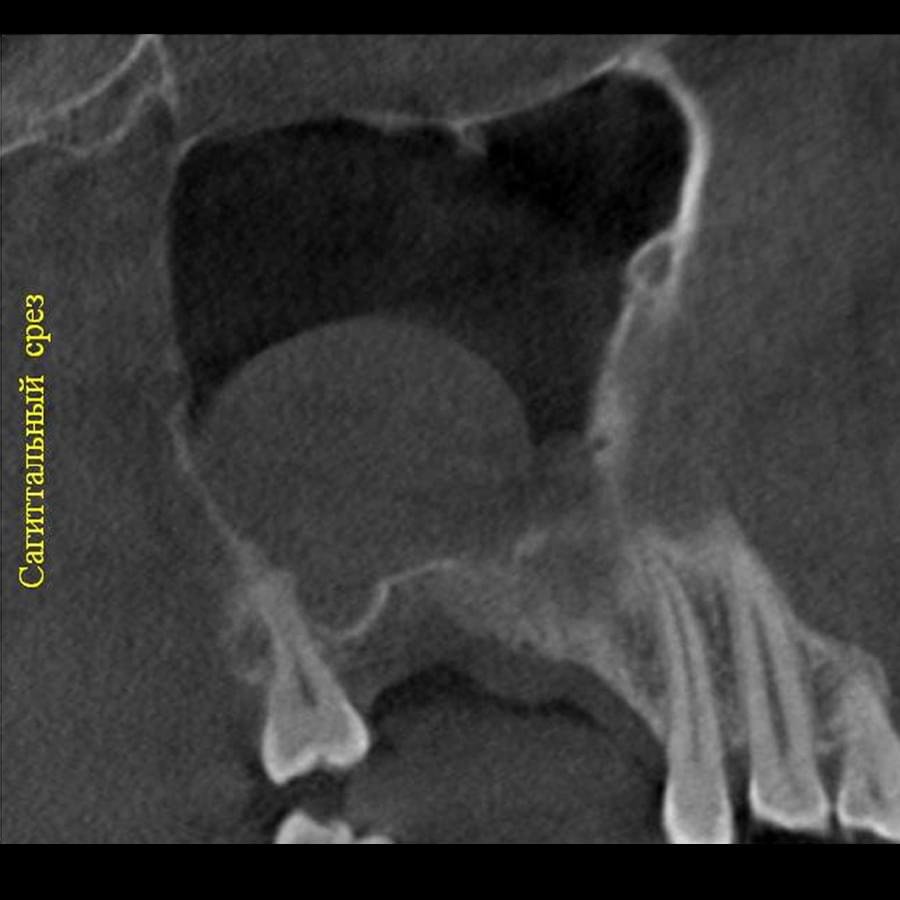

3D цефалометричний аналіз є сучасною технологією, яка дозволяє отримувати точніші,

комплексніші та надійніші дані про зубну та скелетну структуру. Ця технологія може стати

великим кроком в перед для ортодонтів, які хочуть забезпечити найкраще можливе лікування

своїх пацієнтів.

Основні переваги 3D цефалометричного аналізу:

Точність: 3D цефалометричний аналіз забезпечує точніше визначення розмірів та відстаней між

зубами та кістковими структурами.

Комплексність: ця технологія дозволяє отримувати детальні дані про різні структури, такі як

кістка та м'язи, що дозволяє ортодонтам докладніше досліджувати деякі патології та планувати

лікування.

Надійність: 3D цефалометричний аналіз дозволяє отримувати надійніші результати, оскільки

виключає можливість помилок, пов'язаних зі спотворенням або перекриттям зображень.